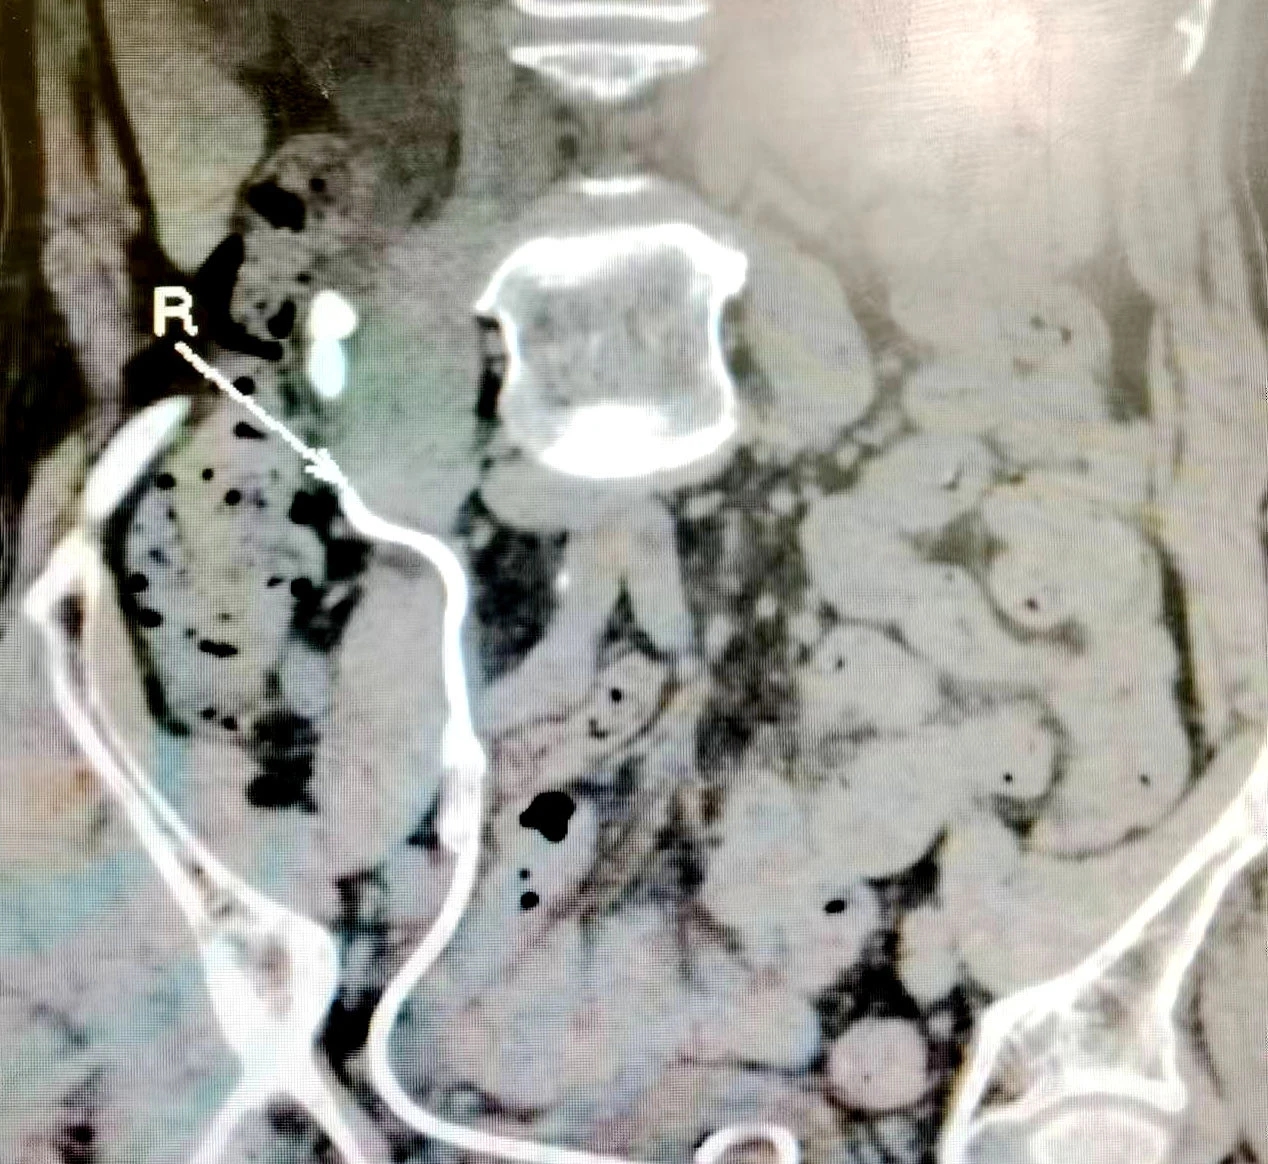

近日,三亚哈医大鸿森医院泌尿外科成功为一位75岁高龄患者完成“首例经尿道输尿管软镜钬激光碎石取石术”,微创、快速、安全、彻底地清除了患者肾脏结石,获得了患者和家属的一致赞扬。今年75岁的方爷爷被肾结石折腾了多年,一直吃药保守治疗,最近因腰痛剧烈,遂来该院泌尿外科就诊,被诊断为“肾积水伴右侧肾输尿管结石”。